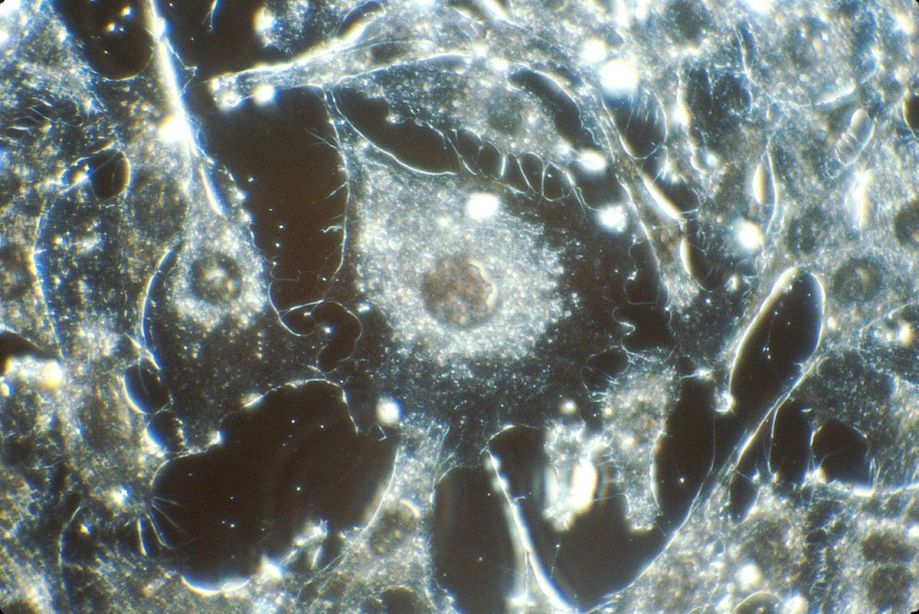

Cancer starts and ends in the human cells. The disease heavily affects these cells and harms the body. In a healthy human body, human cells grow and then divide to form new cells, which is a process called mitosis and meiosis. In a body affected by cancer, however, old cells survive when they should die, and they keep dividing to create more unnecessary cells. These cells are called cancer cells, and they form together to create tumors. There are two different types of tumors: benign and malignant. Benign tumors mean the tumor cannot spread and when it is removed, it will probably not grow back. Benign tumors are easier to handle and sometimes don’t even need to be removed if they aren’t hurting the body. Malignant tumors, on the other hand, can spread to different parts of the body to form new tumors, making it harder to get rid of.

One deadly trait of cancer is that wherever there are cells, cancer can affect it. This makes virtually every part of the body vulnerable to the disease. Depending on the type of cancer, which usually is named in the location of the body it is in, it hurts the body in different ways. For example, lung cancer blocks off part of the lung which doesn’t allow you to inhale the amount of oxygen you need. Brain cancer means a tumor forms in the brain, which can hurt different parts of the brain serving different functions for the body. In these types of cancers and hundreds of others like liver cancer or throat cancer, the tumor is a solid object in the body. In blood cancer, more commonly called leukemia, the tumor is not in a solid state. Starting in the bone marrow, when abnormal cells start growing out of control, also called white blood cells, they interrupt the function of normal blood cells. There are then different types of blood cancers, but leukemia is the most common.